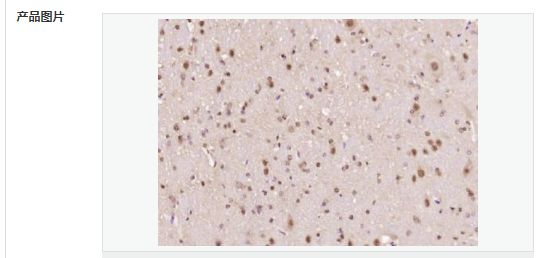

產(chǎn)品介紹The human ataxin-7 gene, also known as spinocerebellar ataxia 7 or SCA7, maps to chromosome 3p13-p12, has a 2,727-bp open reading frame, and encodes a 892 amino acid protein containing a nuclear localization signal and a polyglutamine tract (1,2). SCA7 is an autosomal dominant neurodegenerative disorder characterized by ataxia and selective neuronal cell loss caused by the expansion of a translated CAG repeat encoding a polyglutamine tract in ataxin-7, which is the SCA7 gene product (3,4). Ataxin-7 is expressed within neurons both affected and unaffected in SCA7 pathology with subcellular localization being variable depending upon the neuronal subtype (5). Polyglutamine expanded in ataxin-7 may carry out its pathogenic effects in the nucleus by altering the matrix-associated nuclear structure and/or by disrupting nucleolar function (6).

Ataxin 7 is a protein of unknown function. It may be the human orthologue of the yeast SAGA SGF73 subunit and a subunit of the human TFTC-like transcriptional complexes. Spinocerebellar ataxia 7 (one of a group of hereditary neurodegenrative diseases) is caused by an expanded trinucleotide repeat in the gene encoding ataxin 7. Ataxin 7 is typically located in the cytoplasm and on the nuclear membrane of normal brain neurons. In cells where there is a mutation of the SCA7 gene, ataxin 7 accumulates in intranuclear inclusions and can result in cell death.

細(xì)胞定位細(xì)胞核 細(xì)胞漿